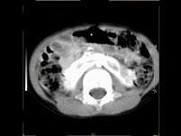

- 多项选择题女,6个月, CT扫描如图所示,下列说法正确的是 ( )

A、双侧肾盂积水

B、双侧肾门朝向前内方

C、双肾下极融合

D、考虑为异位肾

E、考虑为马蹄肾

- 女,6个月, CT扫描如图所示,下列说法